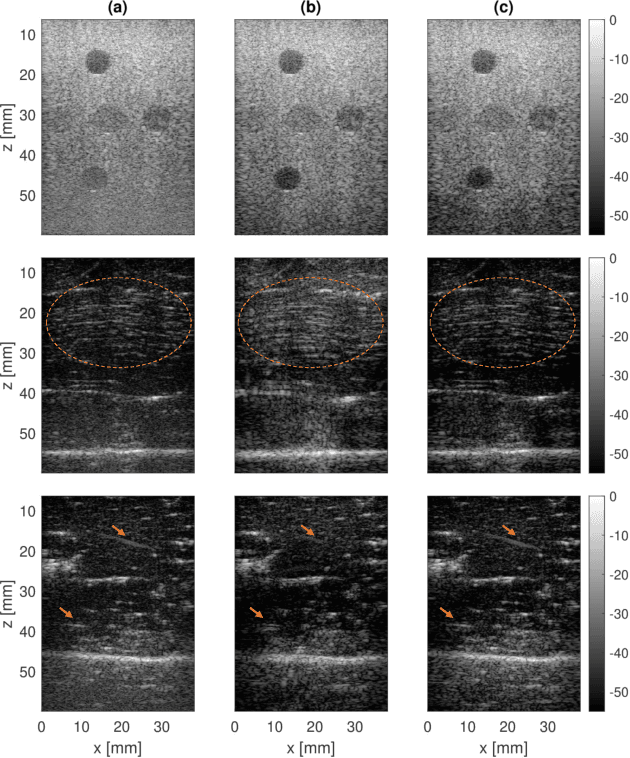

Abstract:Ultrasound images are widespread in medical diagnosis for musculoskeletal, cardiac, and obstetrical imaging due to the efficiency and non-invasiveness of the acquisition methodology. However, the acquired images are degraded by acoustic (e.g. reverberation and clutter) and electronic sources of noise. To improve the Peak Signal to Noise Ratio (PSNR) of the images, previous denoising methods often remove the speckles, which could be informative for radiologists and also for quantitative ultrasound. Herein, a method based on the recent Denoising Diffusion Probabilistic Models (DDPM) is proposed. It iteratively enhances the image quality by eliminating the noise while preserving the speckle texture. It is worth noting that the proposed method is trained in a completely unsupervised manner, and no annotated data is required. The experimental blind test results show that our method outperforms the previous nonlocal means denoising methods in terms of PSNR and Generalized Contrast to Noise Ratio (GCNR) while preserving speckles.

Abstract:During the past few years, inverse problem formulations of ultrasound beamforming have attracted a growing interest. They usually pose beamforming as a minimization problem of a fidelity term resulting from the measurement model plus a regularization term that enforces a certain class on the resulting image. Herein, we take advantages of alternating direction method of multipliers to propose a flexible framework in which each term is optimized separately. Furthermore, the proposed beamforming formulation is extended to replace the regularization term by a denoising algorithm, based on the recent approaches called plug-and-play (PnP) and regularization by denoising (RED). Such regularizations are shown in this work to better preserve speckle texture, an important feature in ultrasound imaging, than sparsity-based approaches previously proposed in the literature. The efficiency of proposed methods is evaluated on simulations, real phantoms, and \textit{in vivo} data available from a plane-wave imaging challenge in medical ultrasound. Furthermore, a comprehensive comparison with existing ultrasound beamforming methods is also provided. These results show that the RED algorithm gives the best image quality in terms of contrast index while preserving the speckle statistics.